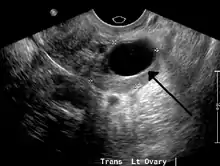

Transvaginal ultrasonography of a hemorrhagic ovarian cyst, probably originating from a corpus luteum cyst. The coagulating blood gives the content a cobweb-like appearance.

Diagnosis

Ovarian cysts are usually diagnosed by ultrasound, CT scan, or MRI, and correlated with clinical presentation and endocrinologic tests as appropriate.[10]

Ultrasound

Follow-up imaging in women of reproductive age for incidentally discovered simple cysts on ultrasound is not needed until 5 cm, as these are usually normal ovarian follicles. Simple cysts 5 to 7 cm in premenopausal females should be followed yearly. Simple cysts larger than 7 cm require further imaging with MRI or surgical assessment. Because they are large, they cannot be reliably assessed by ultrasound alone; it can be difficult to see posterior wall soft tissue nodularity or thickened septation due to limited ultrasound beam penetrance at this size and depth. For the corpus luteum, a dominant ovulating follicle that typically appears as a cyst with circumferentially thickened walls and crenulated inner margins, follow up is not needed if the cyst is less than 3 cm in diameter. In postmenopausal patients, any simple cyst greater than 1 cm but less than 7 cm needs yearly follow-up, while those greater than 7 cm need MRI or surgical evaluation, similar to reproductive age females.[11]